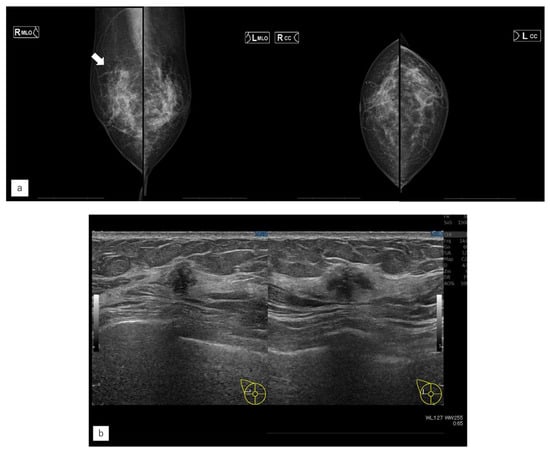

Figure 5.

Representative case (case 7). (a) MG. (b) US. (c) MRI. (d) AI diagnosis. A 63-year-old woman had left-sided breast cancer. Two years later, she was diagnosed with right breast cancer. It was T1c, triple-negative breast cancer. (a) A mass was found in the right upper quadrant via mammography (MG) and diagnosed as a breast imaging reporting and data system (BI-RADS) Category 4. (b) Ultrasonography revealed a hypoechoic mass in the right upper outer quadrant. (c) Magnetic Resonance Imaging revealed a contrast-enhanced mass in the left upper outer quadrant. (d) The artificial intelligence system detected no malignancy. The mass visible on MG was not seen on MG a year earlier. Although the mass was of the same density as the background mammary gland, the radiologists found it to be possibly malignant upon comparison and reading. The malignancy percentage is shown on the left and right sides, respectively (CC: right 1.0%, left 37.5%, MLO: right 3.1%, left 66.5%).